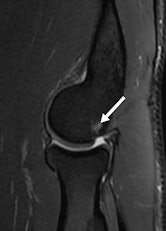

"Elbow injuries in Olympic sports have not been reported previously," noted lead author Dr. Sarath Bethapudi, from the department of musculoskeletal radiology at Leeds Teaching Hospitals National Health Service (NHS) Trust in the U.K. "Most of the injuries resulted from valgus strain with hyperextension of the elbow and usually presented as injuries to the medial joint supporting structures. Combinations of medial and lateral ligaments were seen in combat and power sports with high-energy acute trauma. Such injuries also resulted in tears to secondary stabilizers of the medial joint, including the common flexor tendons and medial muscular compartments" (AJR, September 2013, Vol. 201:3, pp. 535-539).

Of the 28 elbows scanned for acute sports injuries, 15 had high-grade ligament injuries, and 12 of these ligament injuries occurred in contact sports and weightlifting. The remaining three injuries were seen in throwing athletes, two of whom were javelin throwers and one of whom was a volleyball player.

"Tears of the common flexor and extensor tendons occurred in combination with ligamentous injuries. This occurs because common flexors and extensors act as secondary stabilizers of the elbow joint and are injured when the primary stabilizers fail. Once again, these injuries occurred primarily in combat sports, weightlifting, and overhead-throwing athletes," stated Bethapudi, who was responsible for data collection and analysis at the 2012 Olympics and has received funding from GE Healthcare, a sponsor at the games.

Significant ligament and tendon injuries to the elbow can occur often in nonthrowing athletes, and most of the elbow injuries seen in these athletes were isolated high-grade ulnar collateral ligament (UCL) injuries, although combinations of medial and lateral ligament injuries can occur, the authors concluded. Ulnar attachment tears were the next most common injuries, followed by midsubstance tears of the UCL. This trend differs from the existing literature, which suggests that midsubstance tears are the most common type of UCL injuries, they wrote.